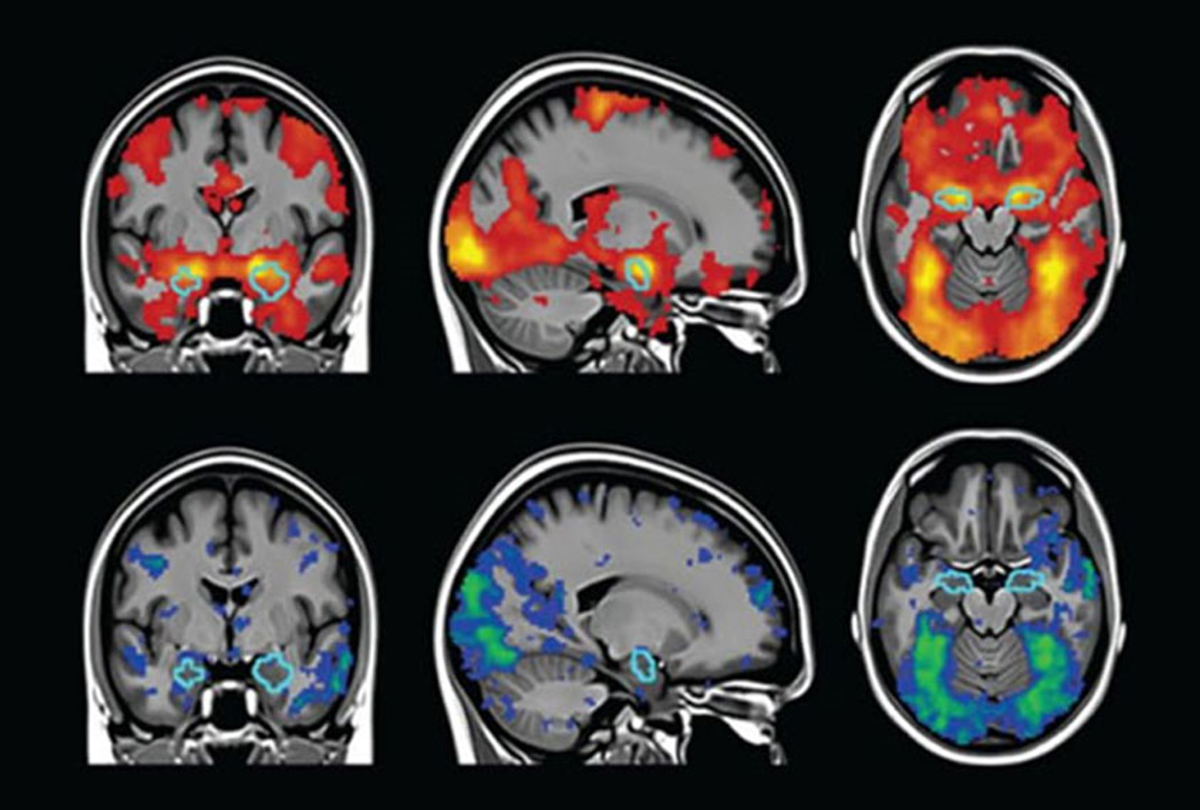

기능적 자기공명영상 (Functional magnetic resonance imaging, fMRI)

: a non-invasive technique for examining brain activity (that creates a dynamic record of metabolic activities over time)